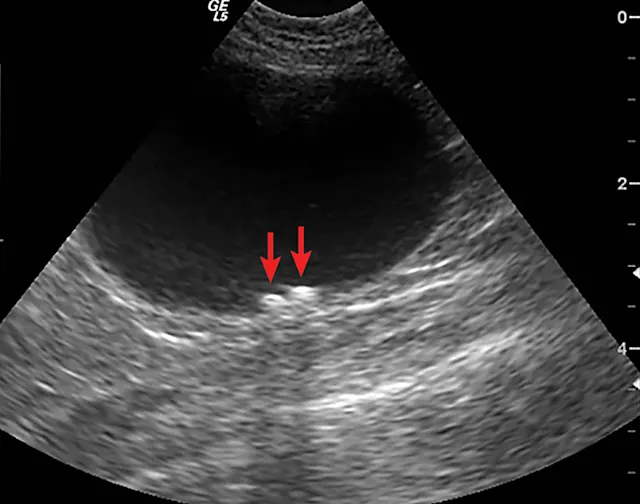

Abdominal radiography and ultrasonography were conducted. Abdominal radiography revealed no abnormalities (Figure 1); ultrasonography revealed 2 small urocystoliths (Figure 2). Medical dissolution was not attempted because the uroliths were not believed to be composed of struvite due to their radiolucency, lack of crystalluria, and aciduria. Because the patient was a male cat, no attempt was made to retrieve the urolith by voiding urohydropropulsion. Percutaneous cystolithotomy1 (Figure 3) was performed. Urocystoliths (Figure 4) were removed and submitted for quantitative analysis.